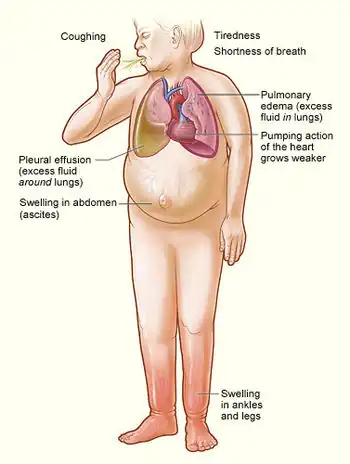

Congestive heart failure is a pathophysiological condition in which the heart's output is insufficient to meet the needs of the body and lungs.[10] The term "congestive heart failure" is often used because one of the most common symptoms is congestion or fluid accumulation in the tissues and veins of the lungs or other parts of a person's body.[10]

Congestion manifests itself particularly in the form of fluid accumulation and swelling (edema), in the form of peripheral edema (causing swollen limbs and feet) and pulmonary edema (causing difficulty breathing) and ascites (swollen abdomen).[29] Pulse pressure, which is the difference between the systolic ("top number") and diastolic ("bottom number") blood pressures, is often low/narrow (i.e. 25% or less of the level of the systolic) in people with heart failure, and this can be an early warning sign.[30]

Symptoms of heart failure are traditionally divided into left-sided and right-sided because the left and right ventricles supply different parts of the circulation. In biventricular heart failure, both sides of the heart are affected. Left-sided heart failure is the more common.[31]

Left-sided failure

The left side of the heart takes oxygen-rich blood from the lungs and pumps it to the rest of the circulatory system in the body (except for the pulmonary circulation). Failure of the left side of the heart causes blood to back up into the lungs, causing breathing difficulties and fatigue due to an insufficient supply of oxygenated blood. Common respiratory signs include increased respiratory rate and labored breathing (nonspecific signs of shortness of breath). Rales or crackles are heard initially in the lung bases and when severe in all lung fields indicate the development of pulmonary edema (fluid in the alveoli). Cyanosis, indicates deficiency of oxygen in the blood, is a late sign of extremely severe pulmonary edema.[32]

Reverse insufficiency of the left ventricle causes congestion in the blood vessels of the lungs so that symptoms are predominantly respiratory. Reverse insufficiency can be divided into the failure of the left atrium, the left ventricle, or both within the left circuit. Patients will experience shortness of breath (dyspnea) on exertion and, in severe cases, dyspnea at rest. Increasing breathlessness while lying down, called orthopnea, also occurs. It can be measured by the number of pillows required to lie comfortably, with extreme cases of orthopnea forcing the patient to sleep sitting up. Another symptom of heart failure is paroxysmal nocturnal dyspnea: a sudden nocturnal attack of severe shortness of breath, usually occurring several hours after falling asleep.[34] There may be "cardiac asthma" or wheezing. Impaired left ventricular forward function can lead to symptoms of poor systemic perfusion such as dizziness, confusion, and cool extremities at rest. Loss of consciousness may also occur due to loss of blood supply to the brain.[35]

Right-sided failure

Right-sided heart failure is often caused by pulmonary heart disease (cor pulmonale), which is typically caused by issues with pulmonary circulation such as pulmonary hypertension or pulmonic stenosis. Physical examination may reveal pitting peripheral edema, ascites, liver enlargement, and spleen enlargement. Jugular venous pressure is frequently assessed as a marker of fluid status, which can be accentuated by testing hepatojugular reflux. If the right ventricular pressure is increased, a parasternal heave which causes the compensatory increase in contraction strength may be present.[36]

Backward failure of the right ventricle leads to congestion of systemic capillaries. This generates excess fluid accumulation in the body. This causes swelling under the skin (peripheral edema or anasarca) and usually affects the dependent parts of the body first, causing foot and ankle swelling in people who are standing up and sacral edema in people who are predominantly lying down. Nocturia (frequent night-time urination) may occur when fluid from the legs is returned to the bloodstream while lying down at night. In progressively severe cases, ascites (fluid accumulation in the abdominal cavity causing swelling) and liver enlargement may develop. Significant liver congestion may result in impaired liver function (congestive hepatopathy), jaundice, and coagulopathy (problems of decreased or increased blood clotting).[37]

Biventricular failure

Dullness of the lung fields when percussed and reduced breath sounds at the base of the lungs may suggest the development of a pleural effusion (fluid collection between the lung and the chest wall). Though it can occur in isolated left- or right-sided heart failure, it is more common in biventricular failure because pleural veins drain into both the systemic and pulmonary venous systems. When unilateral, effusions are often right-sided.[38]